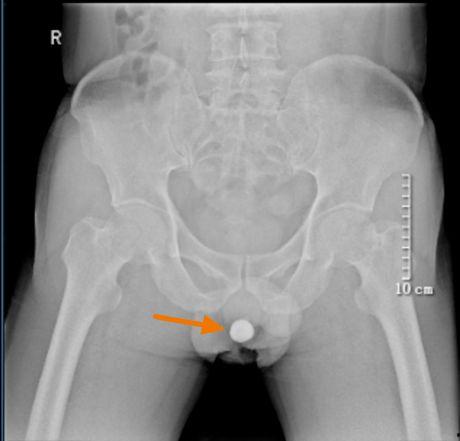

3. 结石:尿路结石是尿道堵的另一个常见原因。结石在尿道中移动时,可能会卡住尿道,导致尿液无法流出。